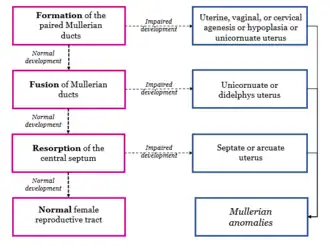

Development

Embryos develop a genital ridge that forms at their tail end and eventually forms the basis for the urinary system and reproductive tracts. Either side and to the front of this tract, around the sixth week develops a duct called the paramesonephric duct, also called the Müllerian duct.[17] A second duct, the mesonephric duct, develops adjacent to this. Both ducts become longer over the next two weeks, and the paramesonephric ducts around the eighth week cross to meet in the midline and fuse.[17] One duct then regresses, with this depending on whether the embryo is genetically female or male. In females, the paramesonephric duct remains, and eventually forms the female reproductive tract.[17] The portions of the paramesonephric duct, which are more cranial—that is, further from the tail-end, end up forming the fallopian tubes.[17] In males, because of the presence of the Y sex chromosome, anti-Müllerian hormone is produced. This leads to the degeneration of the paramesonephric duct.[17]

As the uterus develops, the part of the fallopian tubes closer to the uterus, the ampulla, becomes larger. Extensions from the fallopian tubes, the fimbriae, develop over time. Cell markers have been identified in the fimbriae, which suggests that their embryonic origin is different from that of the other tube segments.[8]

Apart from the presence of sex chromosomes, specific genes associated with the development of the fallopian tubes include the Wnt and Hox groups of genes, Lim1, Pax2, and Emx2.[17]

Embryos have two pairs of ducts that will let gametes out of the body when they are adults; one pair (the Müllerian ducts) develops in females into the fallopian tubes, uterus, and vagina, while the other pair (the Wolffian ducts) develops in males into the epididymis and vas deferens.